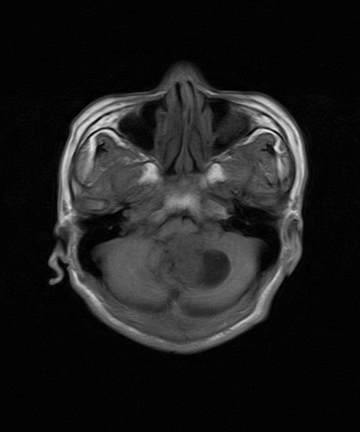

标题: MRI2064:少见病例。男性52,视力下降多年。 [打印本页]

标题: MRI2064:少见病例。男性52,视力下降多年。

四脑室区见混杂信号占位影,脑室系统扩张明显,临近结构显著受压称位,患者52岁,多考虑室管膜瘤可能性大

考虑第四脑室室管膜瘤并阻塞性脑积水。

考虑第四脑室室管膜瘤并梗阻性脑积水;部分性空蝶鞍;左侧上颌窦粘膜下囊肿。

考虑第四脑室室管膜瘤【血供丰富血管母细胞瘤可能】并梗阻性脑积水;部分性空蝶鞍;左侧上颌窦粘膜下囊肿。

小脑蚓部胶质脑膜瘤突入四脑室;肿瘤内见血管流空信号和钙化信号.

比较典型的脉络丛乳头状瘤并脑积水,鉴别小脑蚓部血管母细胞瘤。